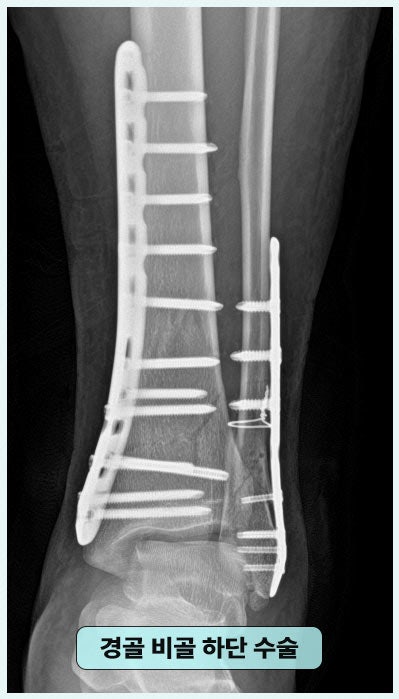

■ 내부 고정술 경골, 비골의 아랫부분은 발목을 접질렀을 때 힘을 집중적으로 받는 부위로 당시 심각한 골절이 발생하였고, 이에 따라 수술 치료가 필요했습니다.

↓ 개방적 정복 및 내 고정술 절개하여 뼈를 제자리에 맞추고 금속 재료로 뼈를 안에서 고정하는 방법